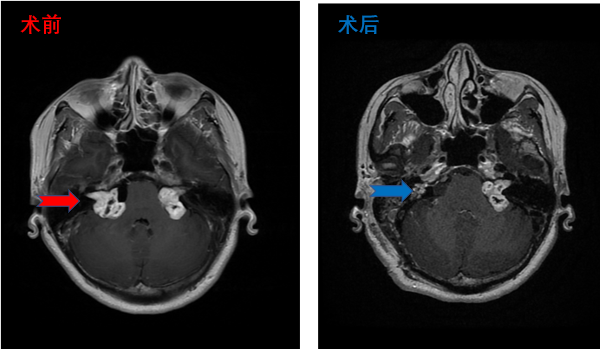

双侧听瘤患者影像,术中右侧面听神经解剖保留,术后右耳听力保留,轻微面瘫,恢复中